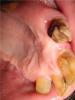

Снял мост для лечения зуба - верхний правый клык, а там вот такая проблема, с левой стороны у корня зуба, похоже зуб немного расплавился - как быть теперь, как то восстоновить реально? Ну и видимо придется одевать коронку и скорее всего сьемный протез в перспективе? Тут на рентгене слева виден фрагмент уже залеченного клыка, а справа ниже, второй опорный зуб моста, шестерка помоему.post-18688-1302599789_thumb.jpgpost-18688-1302599868_thumb.jpgpost-18688-1302599923_thumb.jpg

"Расплавленный" зуб - это вторичный кариес. Такой зуб лучше под ВКВ (Внутрикорневую Культевую Вкладку). Убрав полностью вторичный кариес, от зуба останется "ничего". Только вкладкой надежно восстановить подобный зуб.

Да и остальным зубам, по-моему мнению, тоже грозят ВКВ.